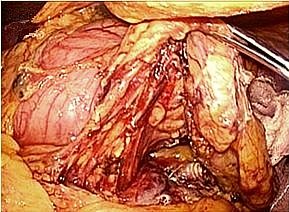

完全腹腔鏡下胃全摘術 (胃の全てを切除する術式)

食道離断 挙上空腸作製

食道−空腸吻合 吻合終了

腹腔鏡下結腸・直腸切除術の実際

全身麻酔下で手術を行います。まず腹腔内(腹腔:お腹の壁と臓器との間の空間のことで

す)に炭酸ガスを入れて膨らませ、お臍からカメラ(腹腔鏡)を挿入します。この際、同

時に手、術操作に用いる器具(鉗子など)を挿入するために、5〜10mmの小さな穴を左

右に4ケ所開けます。そして腹腔鏡で撮ったお腹のなかの様子をモニターに映し出して、

大腸切除や周囲のリンパ節の切除を行います。開腹手術では見えにくかった細かい血管

や神経まで見えて繊細な手術操作が可能です。実際の腹腔鏡手術は、開腹手術と同じ全

身麻酔下で行います。